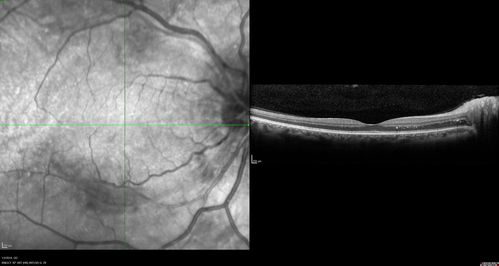

Grade 4 hypertensive retinopathy

55 year old man Hhe did have headaches a few weeks ago and also some nausea and vomiting.  He noticed for a few weeks the vision in the left eye was blurred and  that the vision in the left eye is dark.

VA OD: Dcc20/20

VA OS: Dcc20/100-1

He was admitted directly to ICU for blood pressure control (290 / 170 mmHg)

3 weeks later his VA increased to 20/20 OD, 20/32 OS